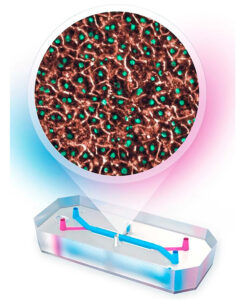

Increíble: UNAM fabrica chip que replica funciones del hígado para evaluar medicamentos

Buenas noticias pues la Universidad Nacional Autónoma de México (UNAM) ha fabricado chip que replica funciones del hígado para evaluar medicamentos. Te contamos los detalles.

UNAM fabrica chip que replica funciones del hígado para evaluar medicamentos